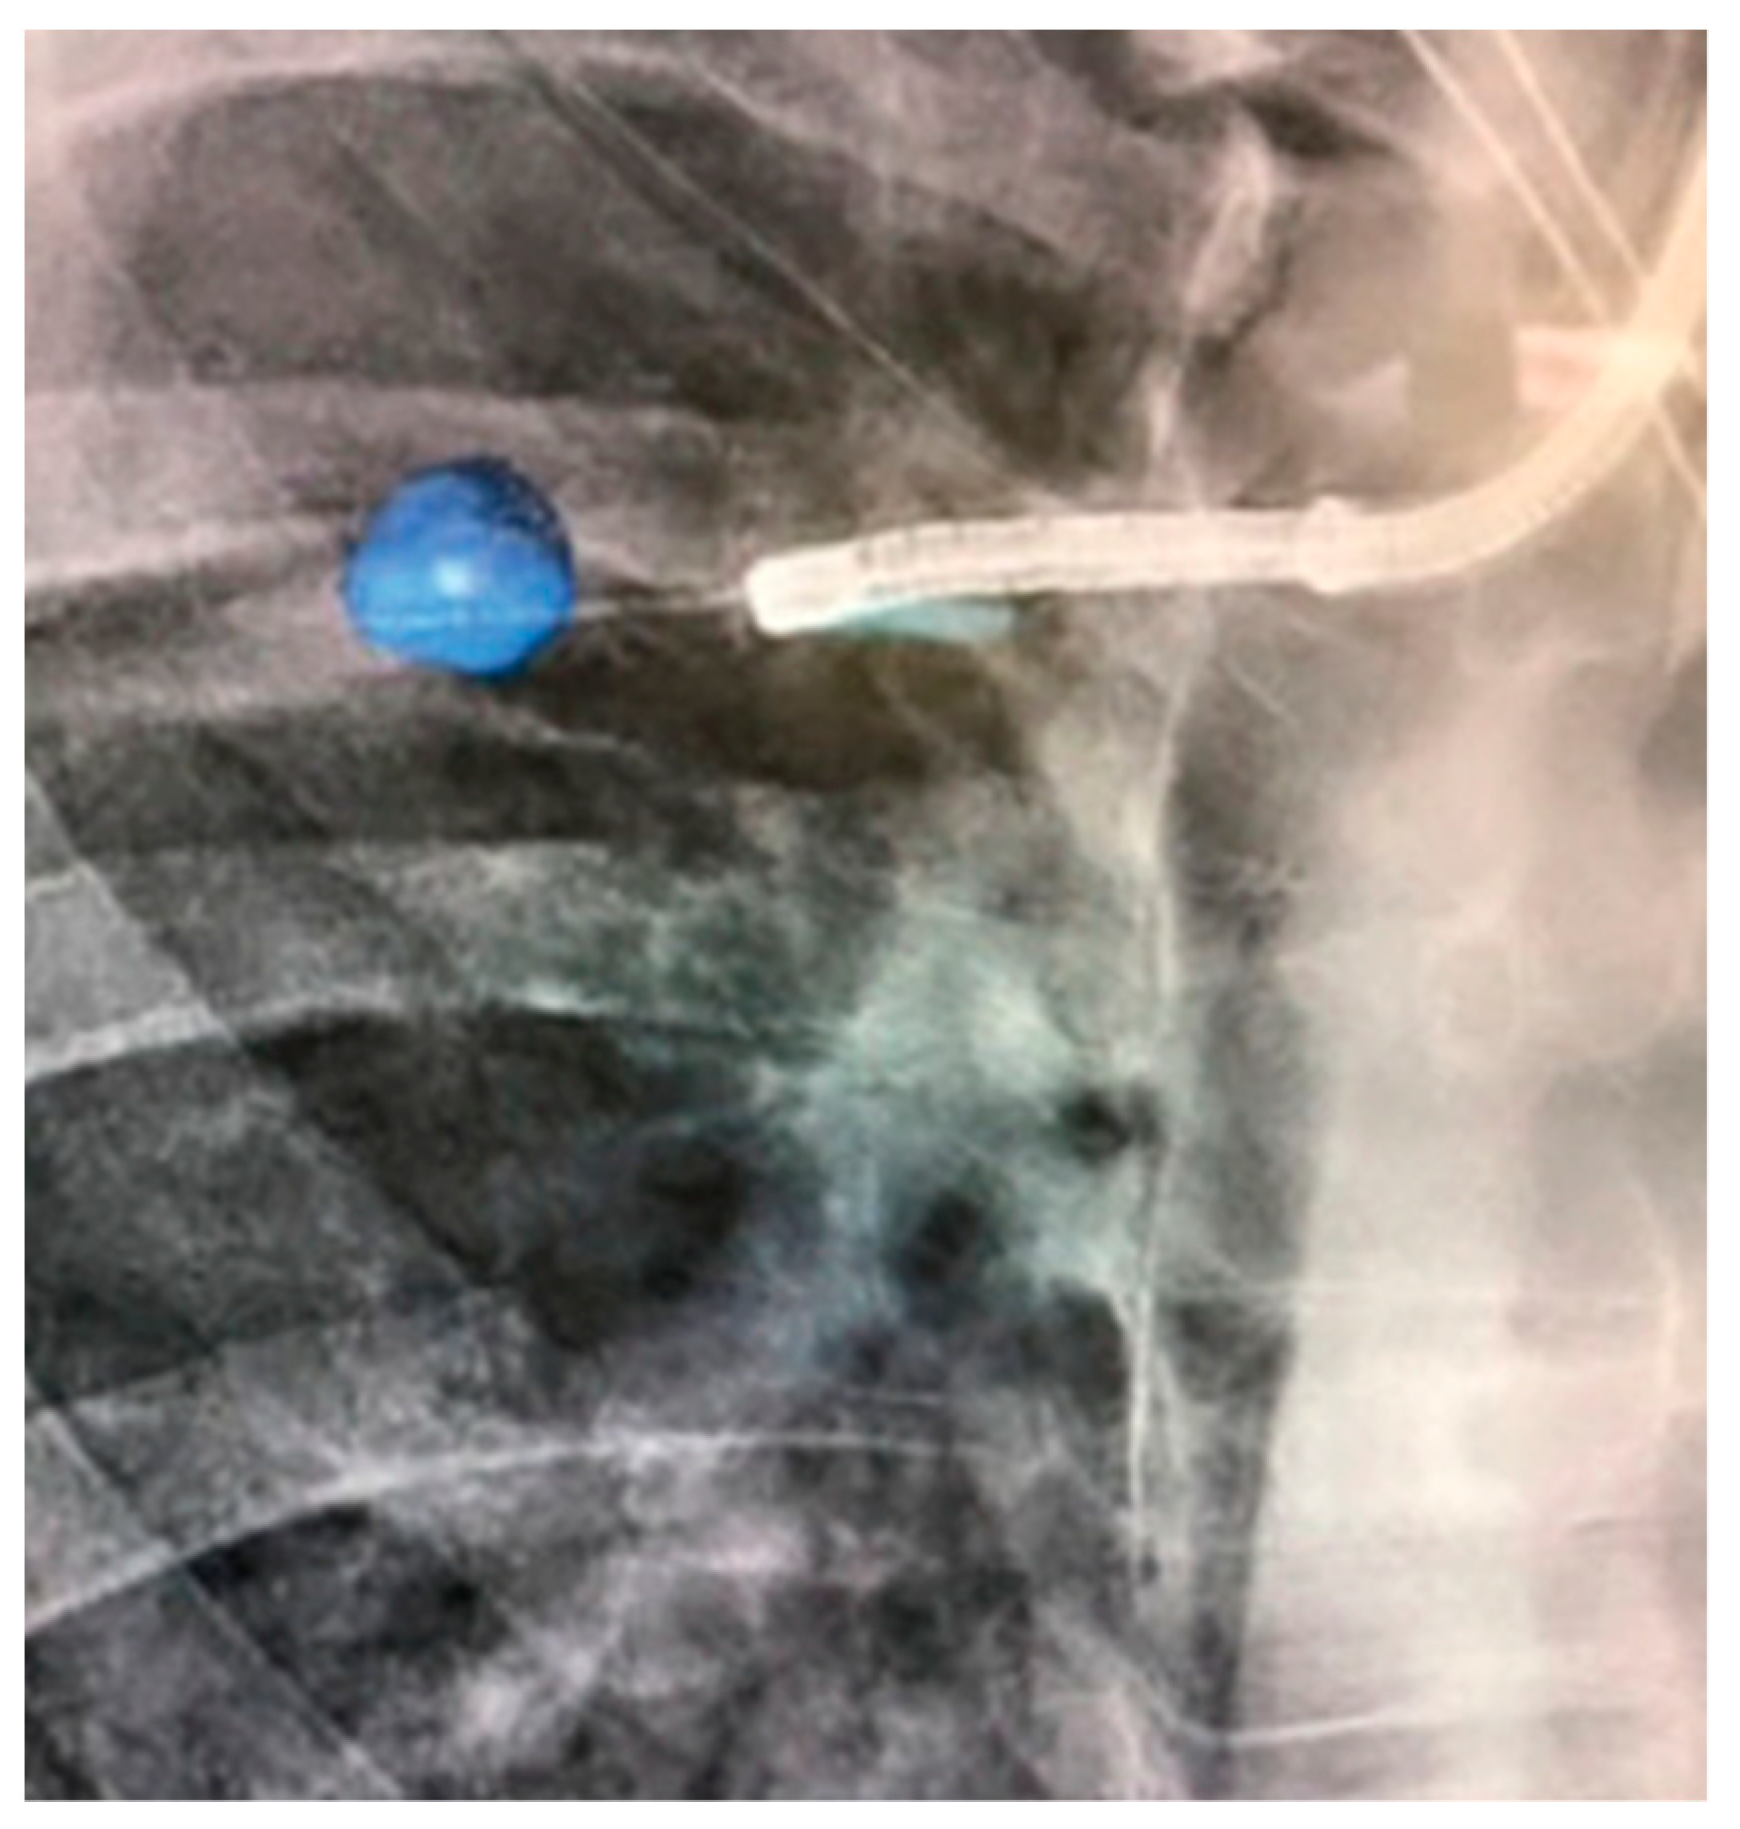

- Chan, J.W.Y.; Lau, R.W.H.; Ngai, J.C.L.; Tsoi, C.; Chu, C.M.; Mok, T.S.K.; Ng, C.S. Transbronchial microwave ablation of lung nodules with electromagnetic navigation bronchoscopy guidance—A novel technique and initial experience with 30 cases. Transl. Lung Cancer Res. 2021, 10, 1608–1622. [Google Scholar] [CrossRef] [PubMed]

- Lau, K.; Spiers, A.; Pritchett, M.; Krimsky, W. P1.05-06 Bronchoscopic Image-Guided Microwave Ablation of Peripheral Lung Tumours—Early Results. J. Thorac. Oncol. 2018, 13, S542. [Google Scholar] [CrossRef]

- Pritchett, M.; Reisenauer, J.; Kern, R.; Wilson, D.S.; Meyers, E.E.; Szapary, P.O.; Laeseke, P.F. Image-Guided Transbronchial Microwave Ablation of Peripheral Primary Lung Tumors with A Flexible Probe: First In Us Experience. Chest 2020, 158, A1452–A1453. [Google Scholar] [CrossRef]

- Zeng, C.; Fu, X.; Yuan, Z.; Hu, S.; Wang, X.; Ping, W.; Cai, Y.; Wang, J. Application of electromagnetic navigation bronchoscopy-guided microwave ablation in multiple pulmonary nodules: A single-centre study. Eur. J. Cardio-Thorac. Surg. 2022, 62, ezac071. [Google Scholar] [CrossRef] [PubMed]